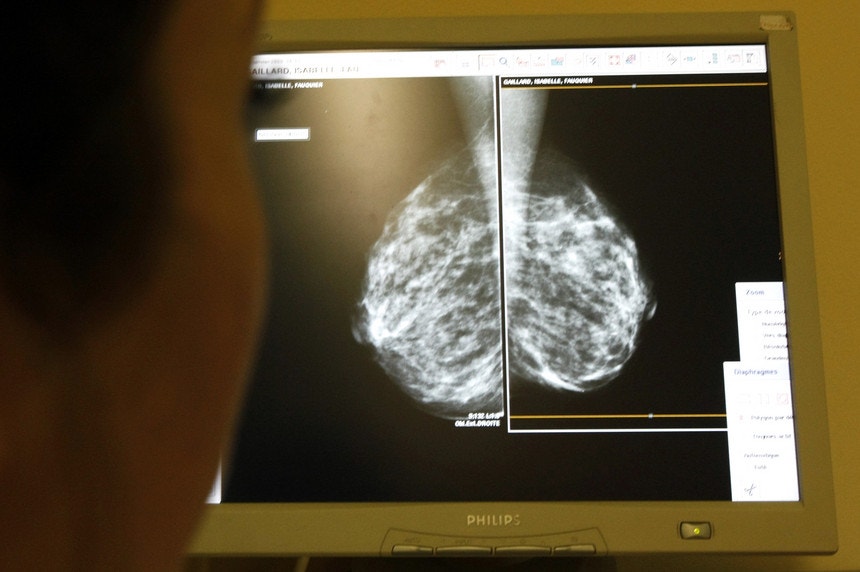

Lusa /

Eric Gaillard - Reuters